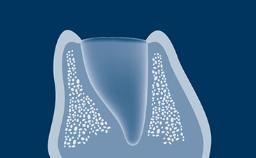

The clinician practicing implant dentistry is confronted with different clinical situations, ranging from a single missing tooth, to an edentulous space with several missing teeth, to complete edentulous ridges.

The prosthesis design must be based on the clinical condition to ensure that the appropriate number of implants are placed in the correct prosthetic positions using implants with appropriate dimensions.